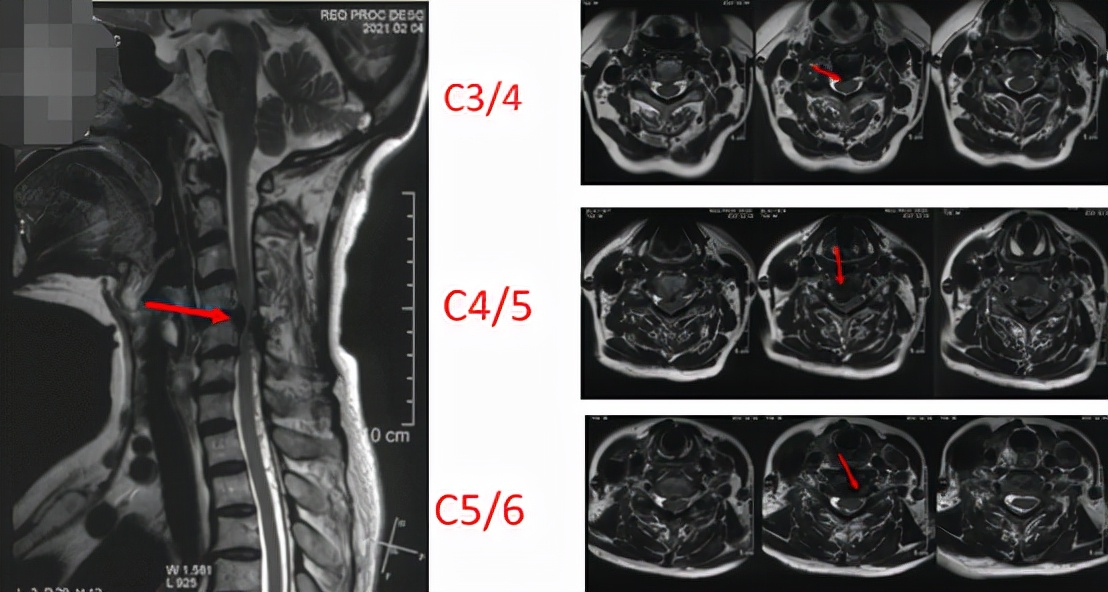

接诊了黄女士后,我为她做了详细的查体,并建议进行颈部的影像学检查。综合各项检查结果发现,原来是黄女士的颈椎出现了问题,她之所以出现这些症状是由于颈椎间盘突出造成了神经根压迫,为神经根型颈椎病。而且黄女士的情况比较严重,多个节段都出现了颈椎间突出,包括颈3/4、颈4/5、颈5/6。此外,还有后纵韧带骨化、颈椎管狭窄。这种情况,我建议黄女士进行手术治疗,将突出的椎间盘髓核切掉,并给神经充分减压。

术前核磁共振(红箭头标的是突出的位置)